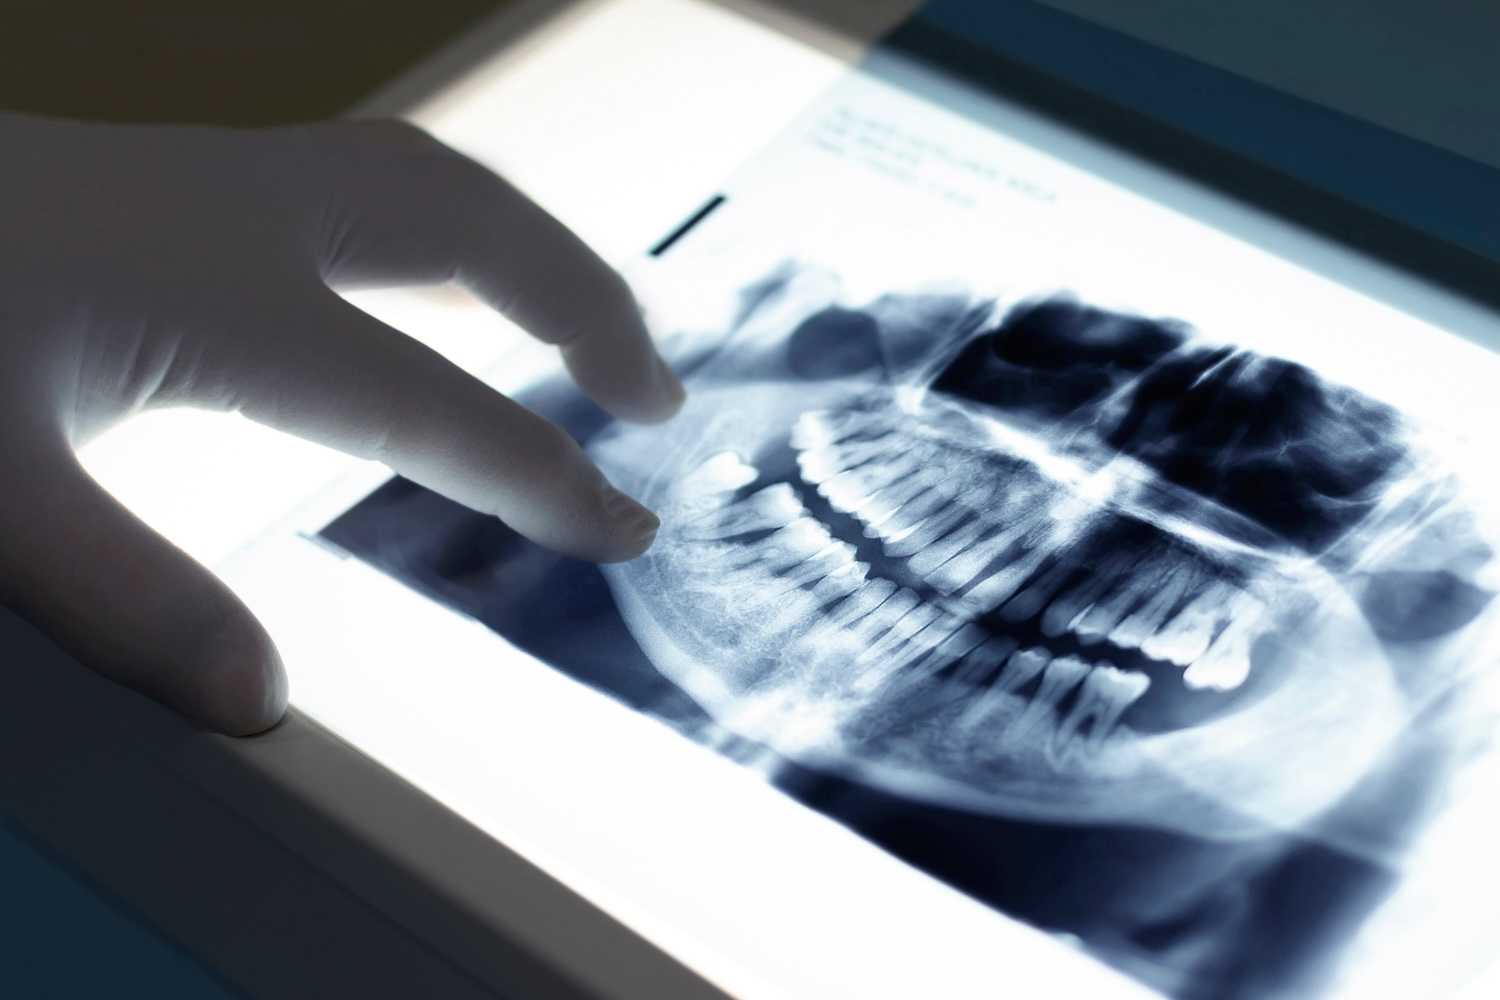

PANORAMA RØNTGEN: Med OPG-røntgen for tannlegen full oversikt over alle tenner og kjevebein. (Foto: Adobe Stock)

Panoramarøntgen (OPG) hos tannlegen

Ortopantomogram, forkortet OPG og ofte kalt panoramarøntgen, gir tannlegen en full oversikt over hele kjeven. De digitale bildene fra panoramarøntgen brukes når man trenger å se:

- Hele tannsettet og kjevebeinet i ett bilde.

- Plassering og utvikling av visdomstenner og andre tenner som ikke har brutt frem.

- Kjeveleddene (TMD).

- Eventuelle patologiske forandringer (cyster, svulster) i kjeven.

- Planlegging av større behandlinger som implantater eller regulering.

Hvordan tas OPG-røntgen?

Du står eller sitter i en spesiell maskin. Du biter forsiktig på en liten holder, og maskinens arm roterer sakte rundt hodet ditt i cirka 15–20 sekunder. Det er viktig å stå helt stille under prosedyren.

Panoramarøntgen er en mer omfattende undersøkelse enn de små intraorale bildene (som bite wing), og krever bruk av en større, mer avansert maskin. Dette gjør at prisen som regel er høyere enn for enkeltvise bite wing-bilder.